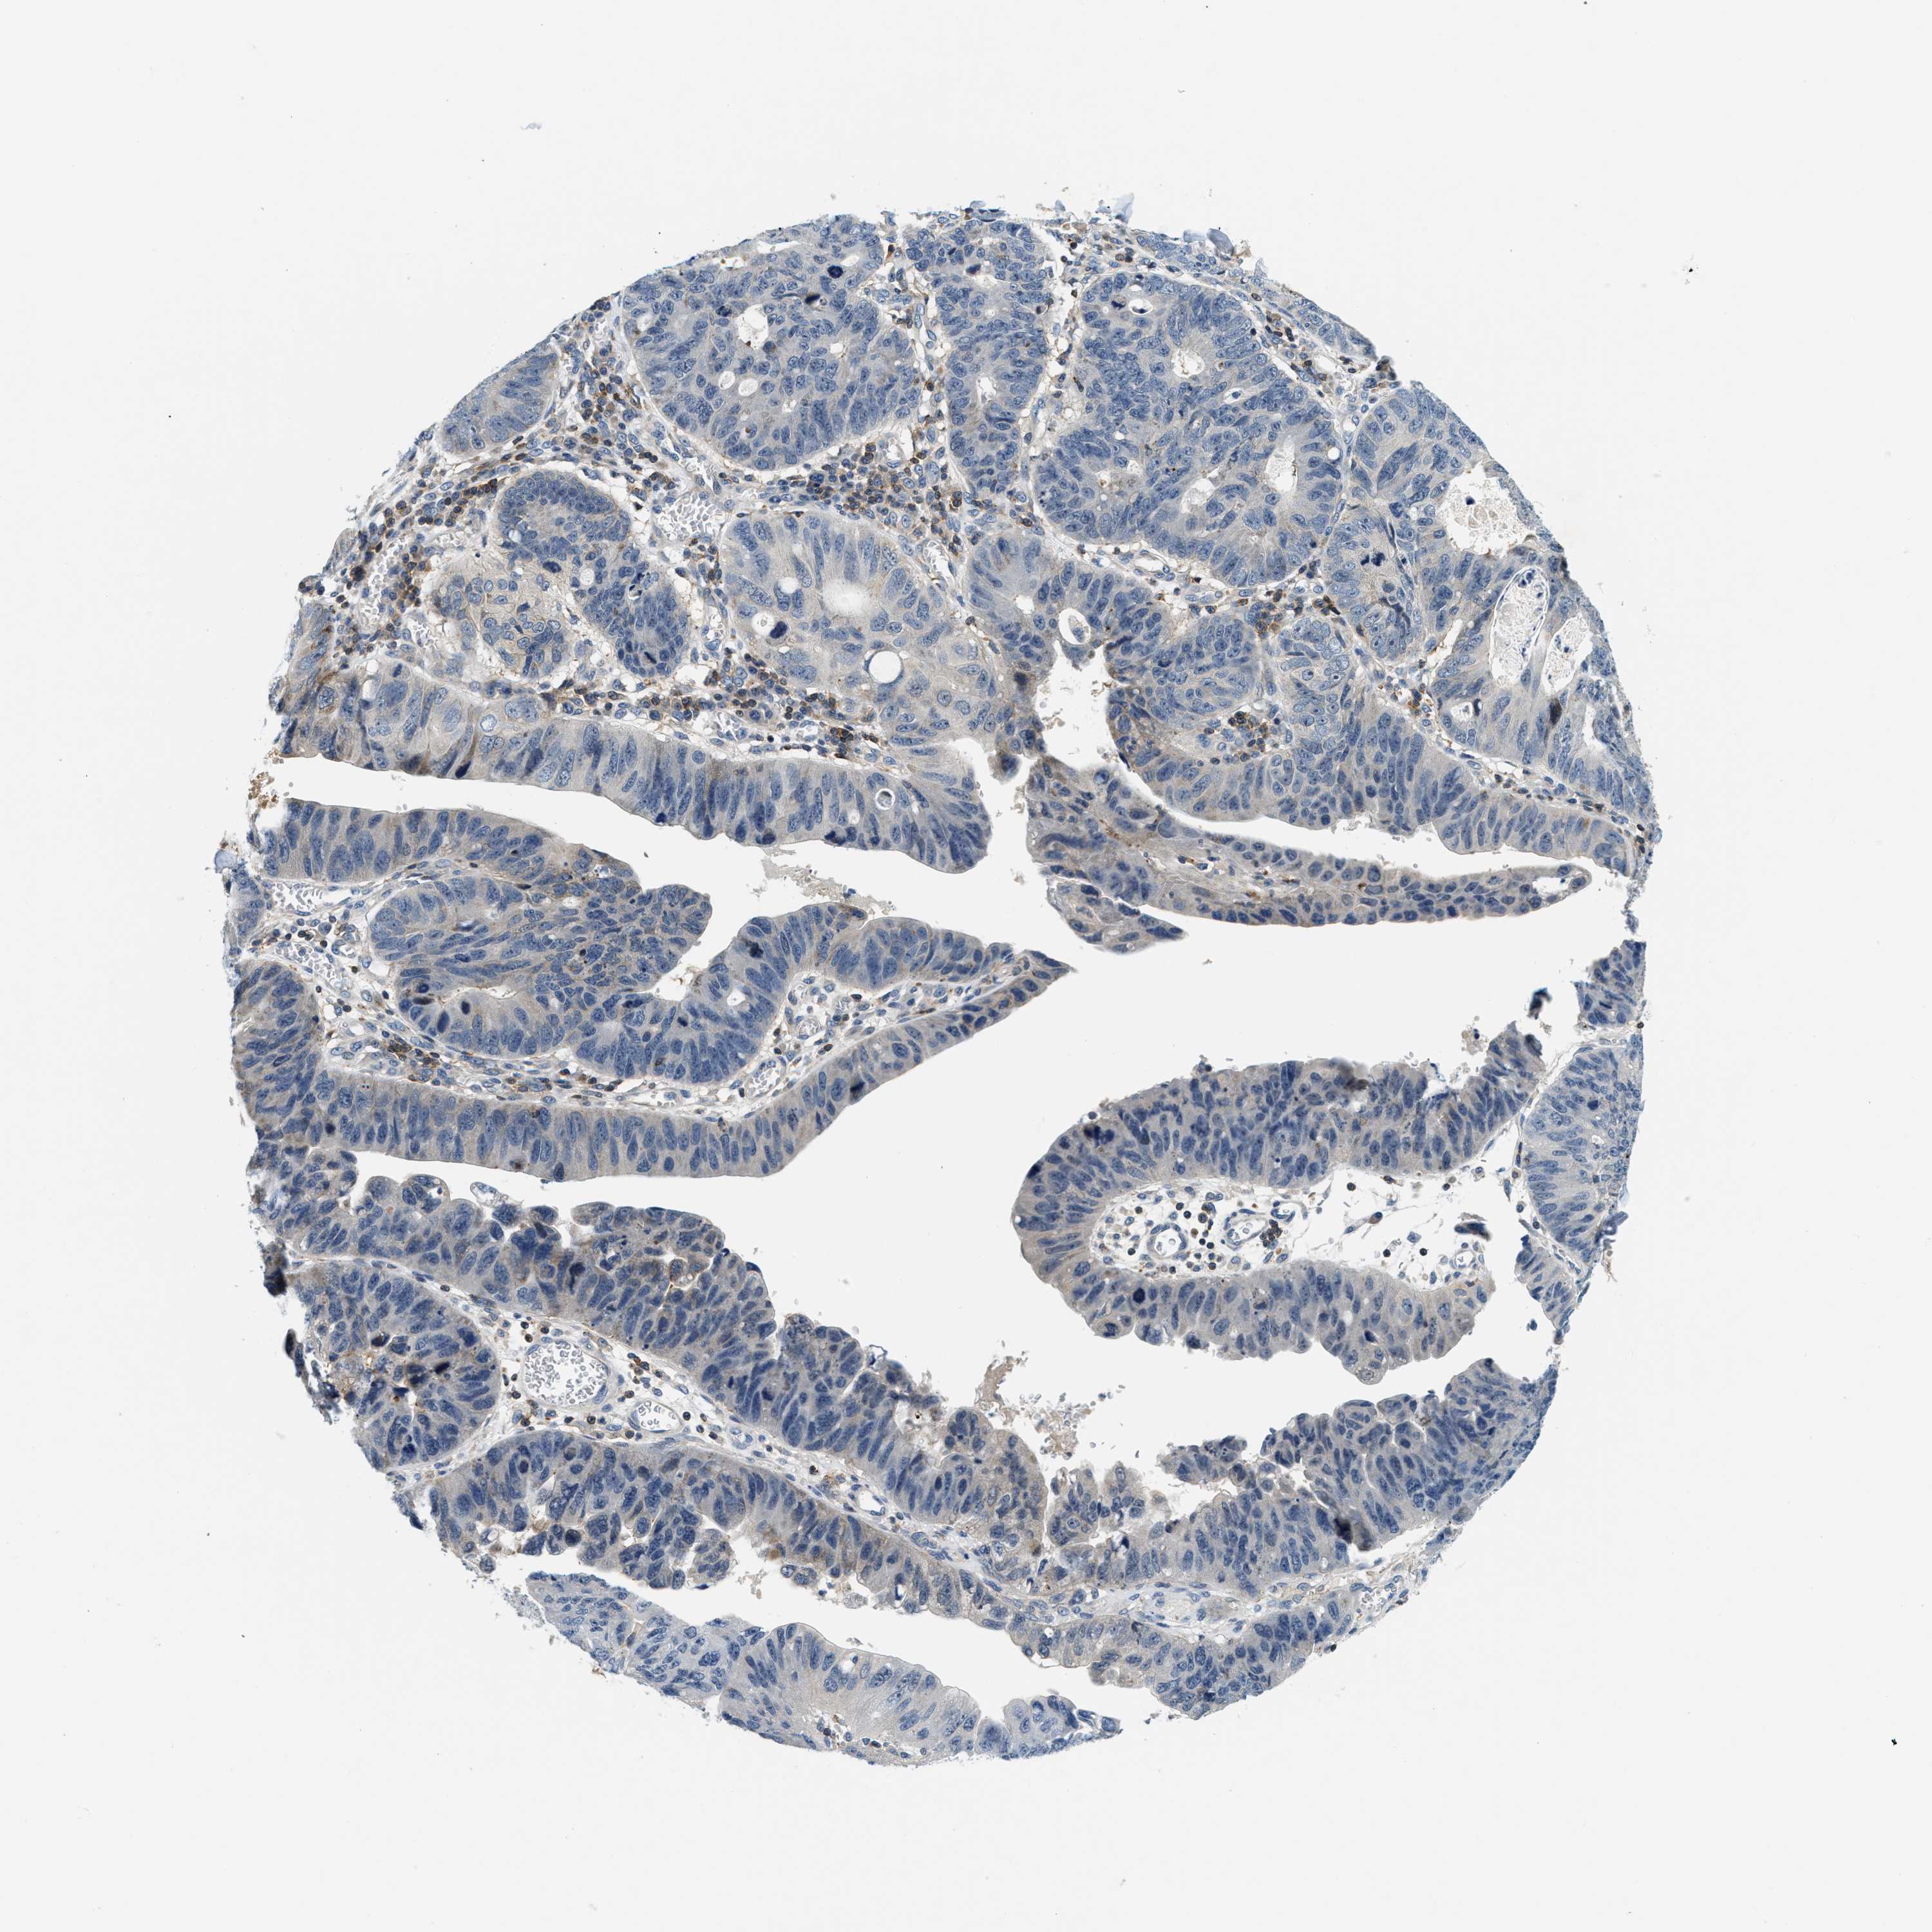

STOMACH CANCER - Protein expressioni

A mouse-over function shows sample information and annotation data. Click on an image to view it in a full screen mode. Samples can be filtered based on level of antibody staining by selecting one or several of the following categories: high, medium, low and not detected. The assay and annotation is described here.

Note that samples used for immunohistochemistry by the Human Protein Atlas do not correspond to samples in the TCGA dataset.

Antibody stainingi

Antibody staining in the annotated cell types in the current human tissue is reported as not detected, low, medium, or high, based on conventional immunohistochemistry profiling in selected tissues. This score is based on the combination of the staining intensity and fraction of stained cells.

Each image is clickable and will lead to virtual microscopy that enables deeper exploration of all samples and also displays staining intensity scores, fraction scores and subcellular localization as well as patient and tissue information for each sample.

Antibody HPA021318

Antibody HPA021319

Staining

High

Medium

Low

Not detected

Intensity

Strong

Moderate

Weak

Negative

Quantity

>75%

75%-25%

<25%

None

Location

Nuclear

Cytoplasmic/membranous

Cytoplasmic/membranous,nuclear

Adenocarcinoma, NOS